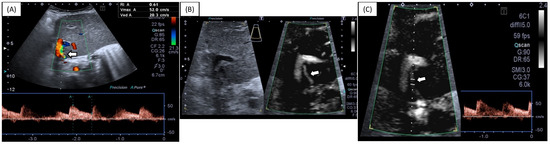

We describe a case of an asymptomatic 70-year-old female patient on whom a carotid ultrasound examination was performed that showed intima–media thickening and a 4 mm long carotid web with a 50% web-to-bulb ratio. Spectral Doppler waveform demonstrated a turbulent flow pattern and [...] Read more.

We describe a case of an asymptomatic 70-year-old female patient on whom a carotid ultrasound examination was performed that showed intima–media thickening and a 4 mm long carotid web with a 50% web-to-bulb ratio. Spectral Doppler waveform demonstrated a turbulent flow pattern and a peak systolic velocity increase of 100% (velocity ratio = 2) when compared with the common carotid artery. Therefore, the patient seemed to be at risk of stroke, and antiaggregant treatment was suggested. Full article